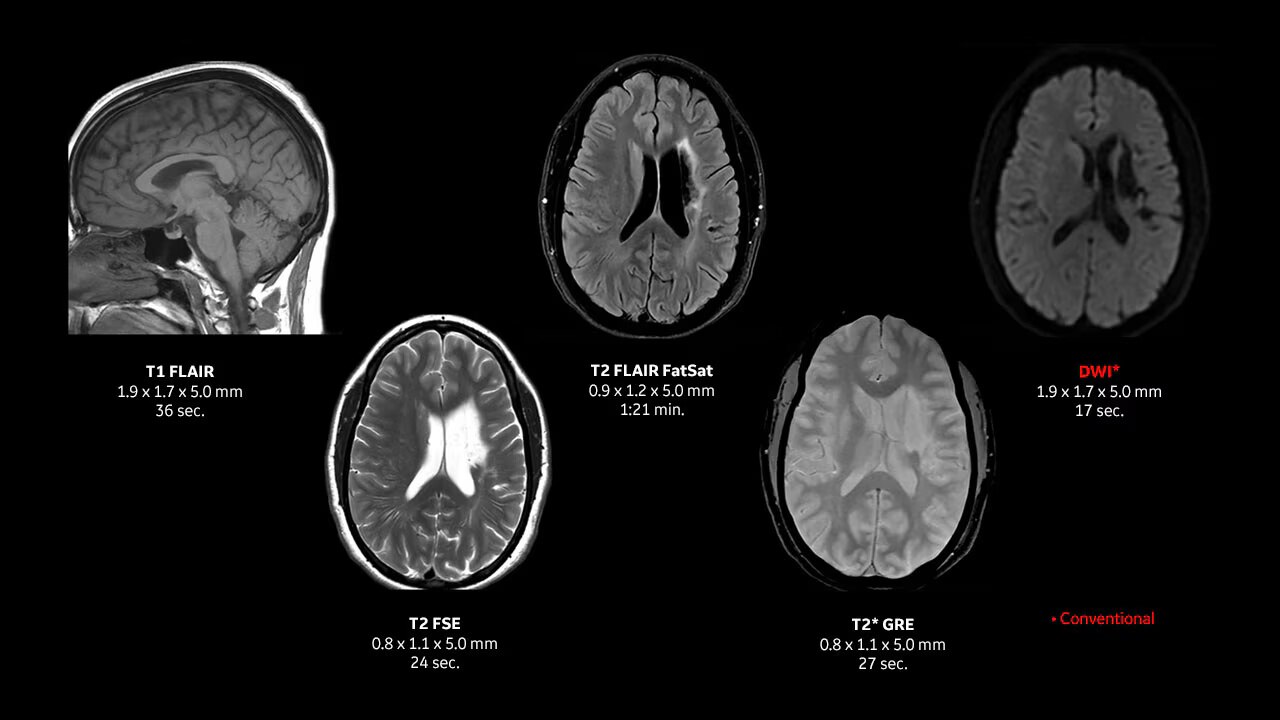

Achieve pin-sharp image quality with pioneering AIR™ Recon DL AI technology.

With access to the latest advanced AI technology, you can scan all anatomies and achieve pin-sharp images. Our pioneering deep learning-based reconstruction algorithm AIR Recon DL accelerates scan time and puts patients at ease.